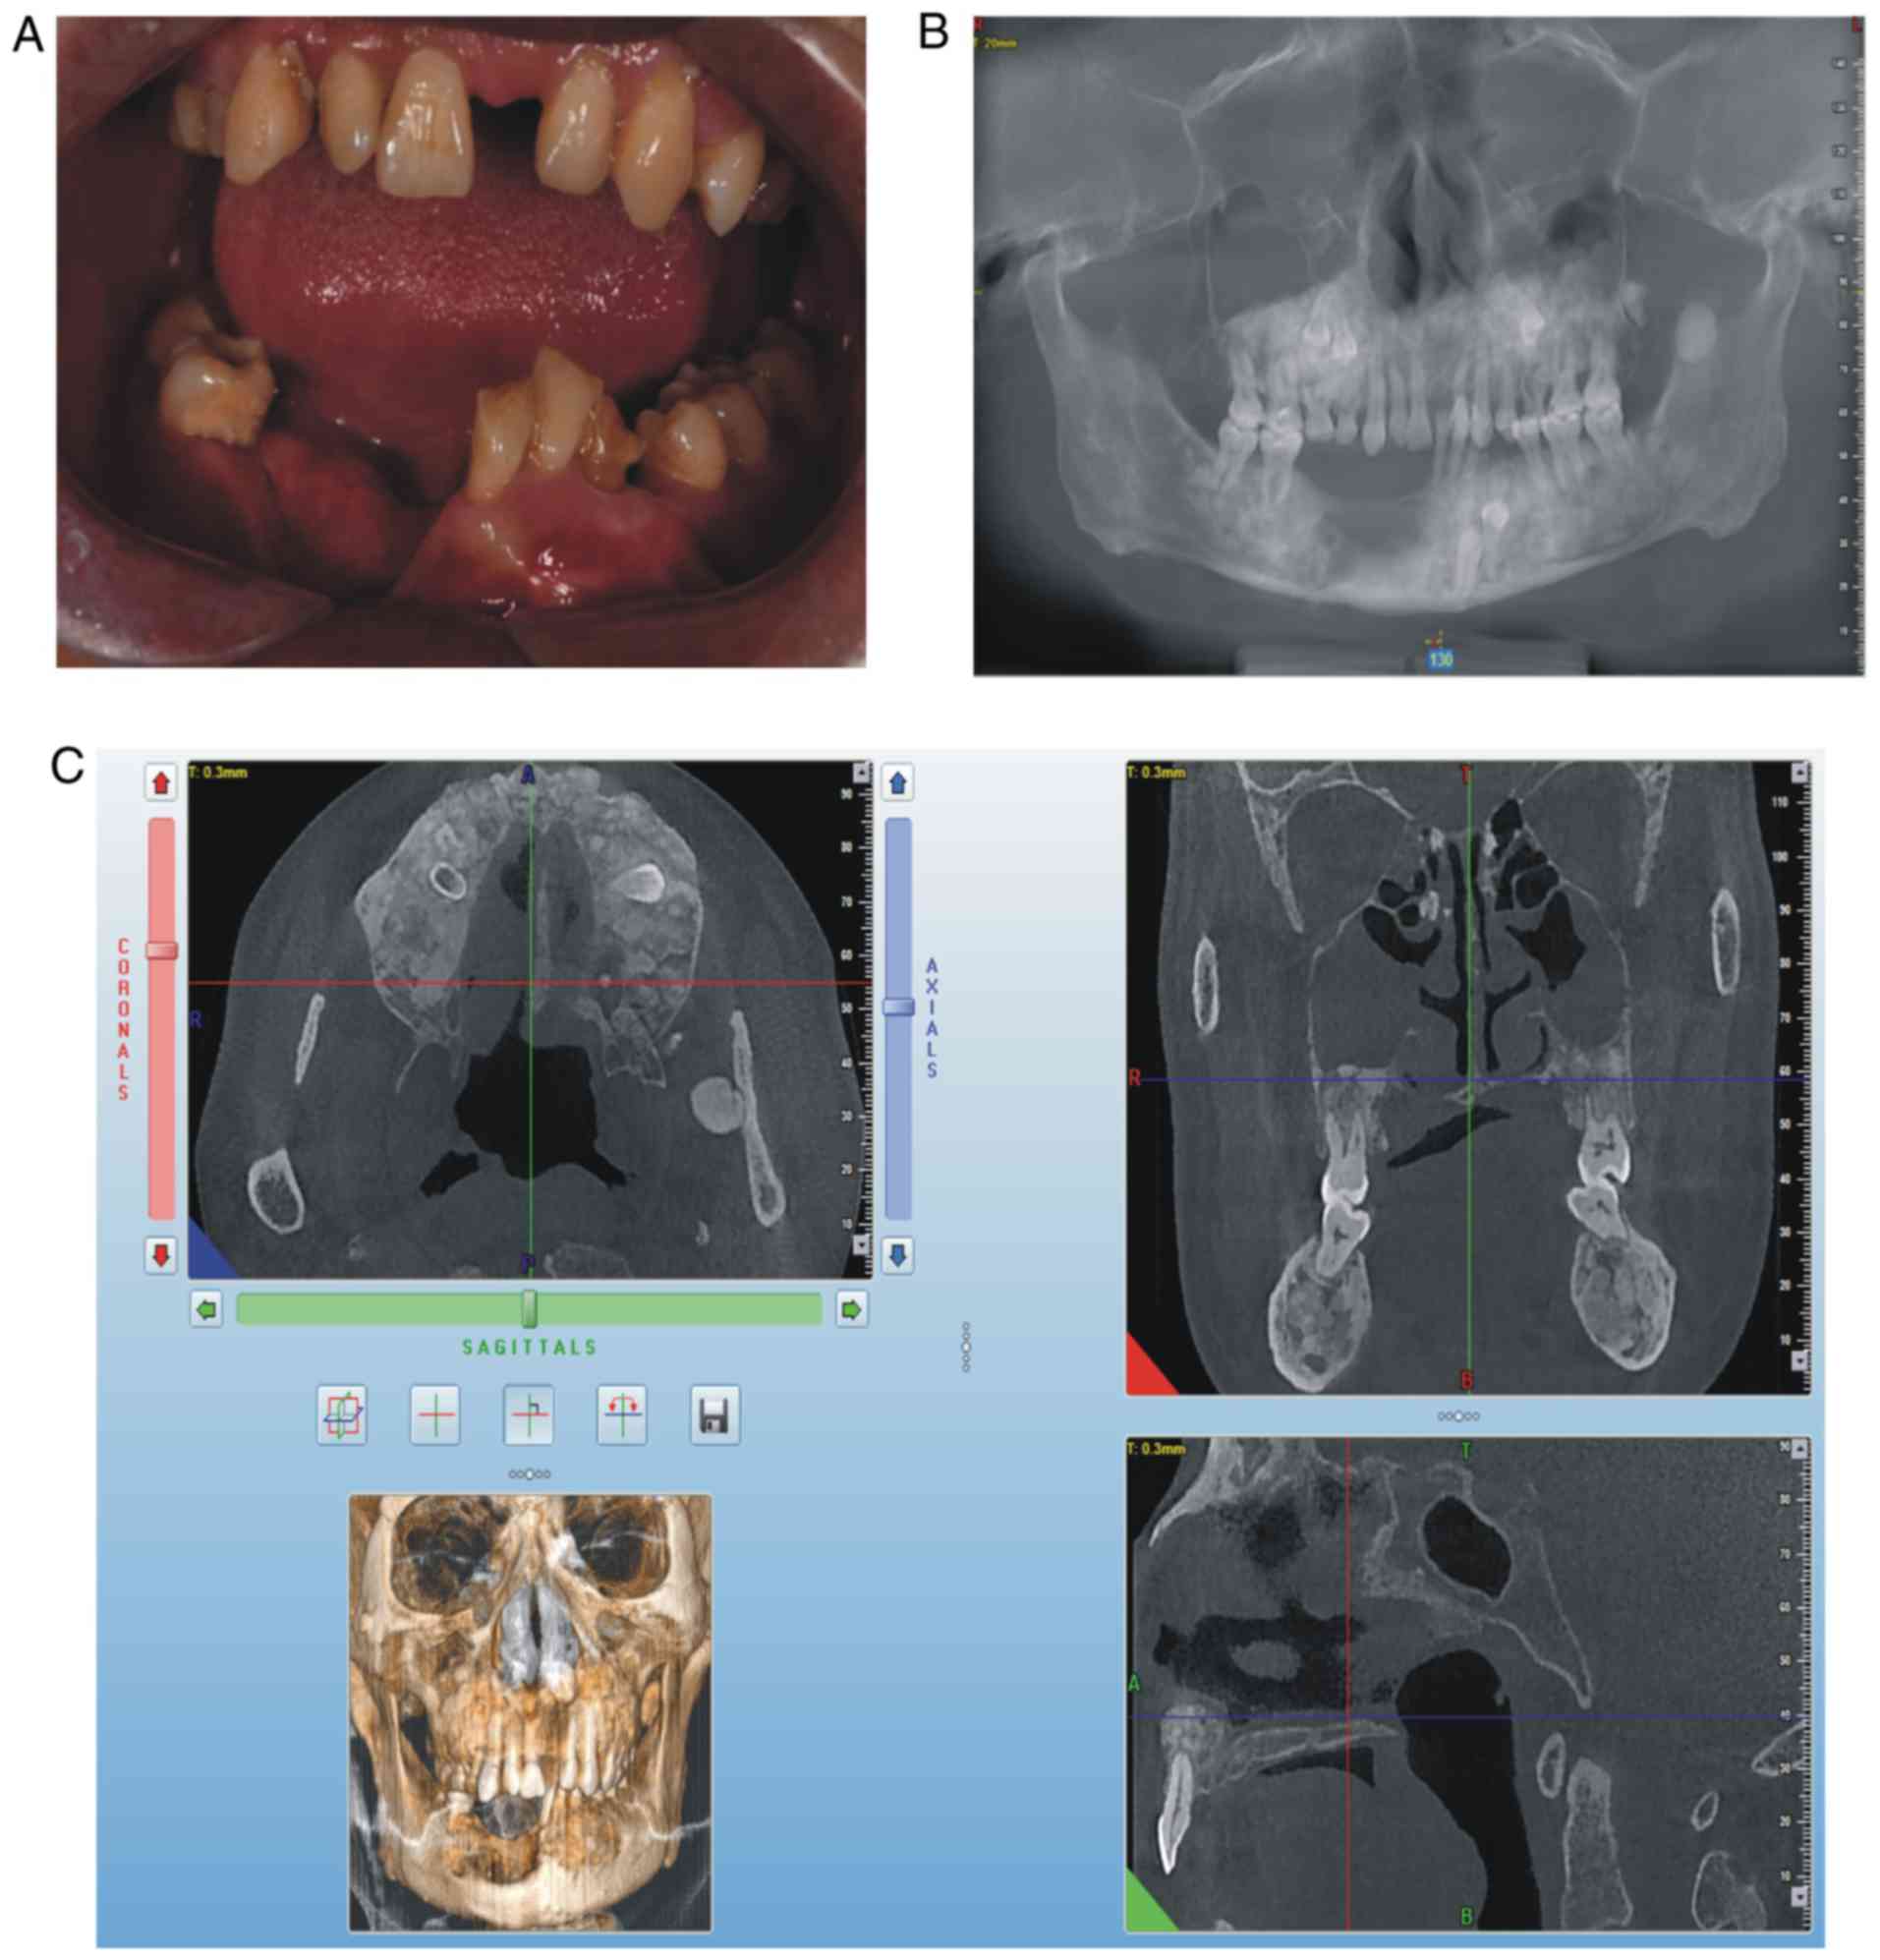

Identification of a mutL‑homolog 1 mutation via whole‑exome sequencing in a Chinese family with Gardner syndrome

Gardner syndrome (GS), a variant of familial adenomatous polyposis, is a rare genetic disorder with autosomal dominant inheritance, characterized by the presence of multiple intestinal polyps, multiple osteomas, dental abnormalities and soft tissue tumors. To date, only a few gene mutations have been demonstrated to be responsible for GS. To explore potential unknown mutations responsible for GS, the present study used whole‑exome sequencing of two affected individuals from a family with GS to identify a candidate mutation in mutL‑homolog (MLH)1. The two patients with GS were diagnosed based on a combination of clinical features, family history, physical examinations and cone‑beam computed tomographic imaging. Through whole‑genome sequencing, the present study subsequently identified a missense mutation in MLH1 (NM_000249.3:p.Tyr379Ser/c.1136A>C), which was further confirmed by Sanger sequencing. Furthermore, the amino acid residue p.Tyr379 was identified to be highly conserved among different species through sequence alignment with ClustalW2. In conclusion, the results identified for the first time a MLH1 missense mutation (NM_000249.3:​p.Tyr379Ser/c.1136A>C) in a Chinese family with GS, thus broadening the range of mutated genes associated with GS. This highlights the value of whole‑exome sequencing in identifying disease mutations in a family.